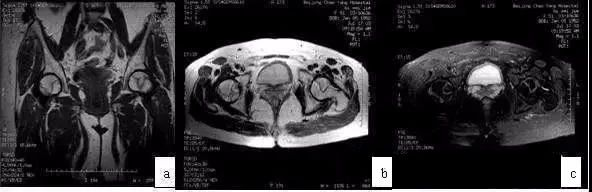

您是否正在被不明原因的髋部(俗称“胯部”)疼痛所困扰?这种疼痛有时还牵连到大腿根或膝盖,走路时加重,休息后缓解?这背后,可能隐藏着一种名为“股骨头坏死”的隐形杀手。而有一种检查,能像侦察兵一样,在疾病造成不可逆损害前,能早早地将其“缉拿归案”,它就是——磁共振(MRI)检查。 股骨头坏死(ONFH)通常是由于股骨头血供中断或受损,导致骨细胞及骨髓成分死亡的病理过程。常见高危因素包括:激素应用、酗酒、髋部外伤等。 该疾病进展性强,若不及早干预,股骨头力学结构破坏,最终将发生塌陷,导致髋关节功能严重丧失,届时只能行人工关节置换术。 在疾病早期,X线平片只能显示骨骼的大体形态。此时股骨头形态完好,X线片可表现为完全正常。当X线片上出现阳性改变时,往往已非早期,部分患者已出现股骨头塌陷,错过了最佳治疗时机。 CT的敏感性虽高于X线,但对仅存在于骨髓的早期坏死病灶依然不敏感。 磁共振(MRI)是当前诊断早期股骨头坏死最敏感、最特异的影像学方法,被公认为“金标准”。 其核心优势在于: * 极高的敏感性:在骨细胞发生坏死、但股骨头外形尚未改变时,MRI即可清晰显示骨髓水肿及典型的“线样征”,这是早期诊断的直接依据。 * 精准分期与评估:MRI能精确显示坏死灶的位置、范围,评估周围骨髓水肿情况,为临床医生制定个体化“保髋”治疗方案提供最关键的依据。 典型的早期股骨头坏死MRI图像(a)T1WI带状低信号;(b)T2WI双线征;(c)T2WI抑脂像示带状高信号 髋关节是承载我们自由行走的关键。当它发出疼痛的预警时,我们不应止步于一张“正常”的X光片报告。磁共振以其无辐射、高分辨率和无可比拟的早期诊断能力,成为了髋关节疾病的重要诊断方式。